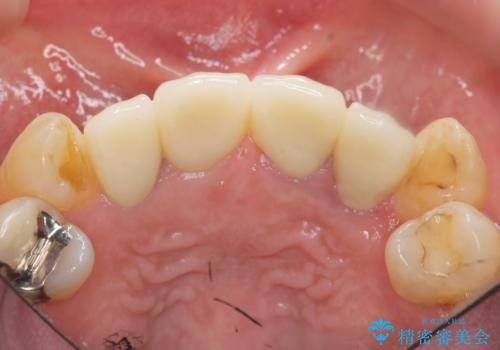

前歯の見た目をオールセラミッククラウンで改善

- 前歯のぐらつき、見た目の改善を希望され来院されました。

ぐらつきのある歯は、破折が認められ、その他前歯も不十分な根管治療や不適合なクラウン、レジン修復により審美障害が起きています。

問題を一つづつ丁寧に解決し、前歯の審美性の改善を計画します。

オールセラミックによる審美的な仕上がりに満足いただくことができました。